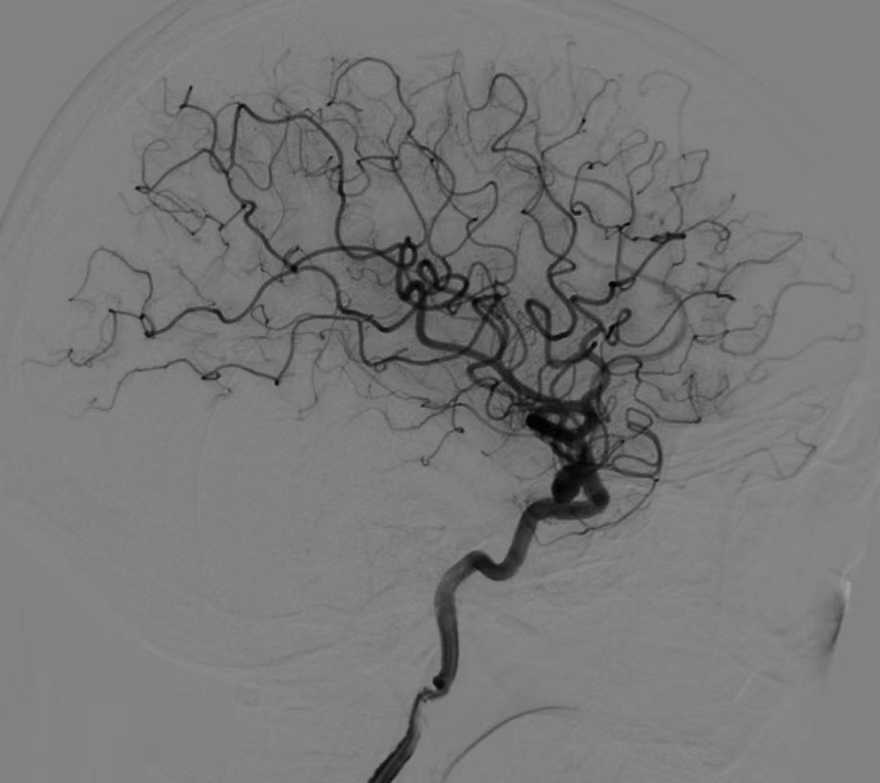

正常脑血管造影:血管有粗到细逐渐分支

烟雾病患者血管造影:血管像冒烟一样